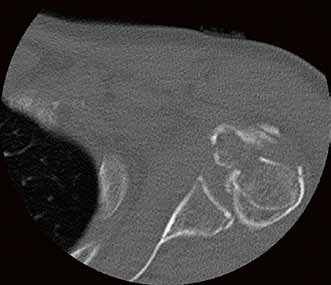

Die Klinik verfügt über 14 Computertomographen (CT), zwölf Magnetresonanztomographen (MRT) sowie zahlreiche Ultraschallgeräte. Allein am Campus Benjamin Franklin führen die Radiologen an sieben Tagen die Woche je zwischen 50 und 60 CT Untersuchungen täglich durch. Seit knapp drei Monaten steht ihnen dazu der neue 160-Schicht-Low-Dose-CT Aquilion PRIME zur Verfügung. Ein weiterer Aquilion PRIME sowie ein 640-Schicht-Volumen-CT Aquilion ONE ViSION EDITION wurden am Campus Mitte installiert. „Als wir nach einem neuen CT gesucht haben, war klar, dass dessen Ausstattung allen universitären diagnostischen Anforderungen gerecht werden muss", erklärt Dr. Stefan Niehues, Radiologe und Oberarzt der Klinik für Radiologie am Campus Benjamin Franklin.

„Mit dem neuen CT Aquilion PRIME können wir das komplette radiologische Spektrum der Charité abdecken. „Die gesamte Polytrauma-Diagnostik über die Akutversorgung bis hin zur Neuroradiologie und Diagnostik bei jungen Menschen führen wir mit dem Aquilion PRIME durch."

Neben der Rechnergeschwindigkeit lautet das Schlüsselwort bei dem neuen Gerät „Adaptive Iterative Dosis-Reduktion (AIDR 3D)". „Dieser mathematische Algorithmus erlaubt es uns, mit einem Bruchteil der Dosis zu arbeiten, die wir bisher für die erforderliche Bildqualität benötigt haben", weiß der Radiologe.

„Durch die Spitzentechnologie können wir bei gleich hoher Bildqualität die Dosis an Röntgenstrahlung bei vielen Untersuchungen auf ein Drittel reduzieren."